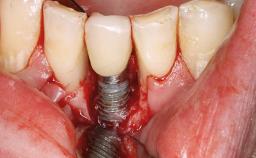

Peripheral Giant-cell Granuloma Associated with Peri-implant Tissues

Giant-cell granulomas (GCG) of the jaws are benign reactive lesions of unknown etiology, unrelated to giant-cell tumors (osteoclastomas), which are defined as benign but locally destructive and aggressive neoplasms (Jundt and coworkers 2005). Depending on their localization at the initial diagnosis, GCG are dived into central (CGCG) and peripheral (PGCG) types. CGCGs occur within the jawbones and appear as unilocular or multilocular radiolucent lesions. The incidence in the general population is very low. They are more commonly found in the mandible, mainly in children and young adults—patients are generally younger than 30 years—and have a greater incidence in females (Heithersay and coworkers 2002). The clinical behavior of CGCGs varies from slowly growing asymptomatic swellings to aggressive lesions that may result in pain, cortical perforation of the affected jaw site, and root resorption (de Lange and coworkers 2007).

# of Implants 5

Type of Implants One-Piece